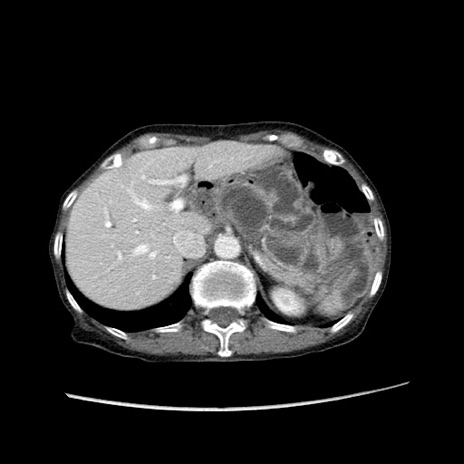

症例25(横断像)

【症例】80歳代女性

【主訴】胸のつかえ感

【現病歴】約9時間前に食後から胸のつかえた感じあり、嘔吐あり、来院。

【既往歴】胃癌(全摘)、胆摘、虫垂炎

【身体所見】心窩部に圧痛あり、反跳痛なし。

【データ】WBC 5700、CRP 0.05